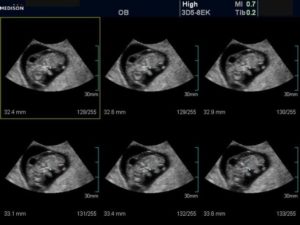

При ультразвуковом исследовании врач производит некоторые замеры и расчеты для определения количества околоплодных вод, после чего делает заключение о маловодии, нормальном количестве вод или о многоводии.

- ультразвуковое исследование и допплерографию, в результате которых можно:

- определить количество воды в плодном яйце;

- уточнить степень отставания ребенка в развитии;

- оценить качество кровотока в маточных артериях беременной женщины, а также в пуповине и мозговой артерии плода.